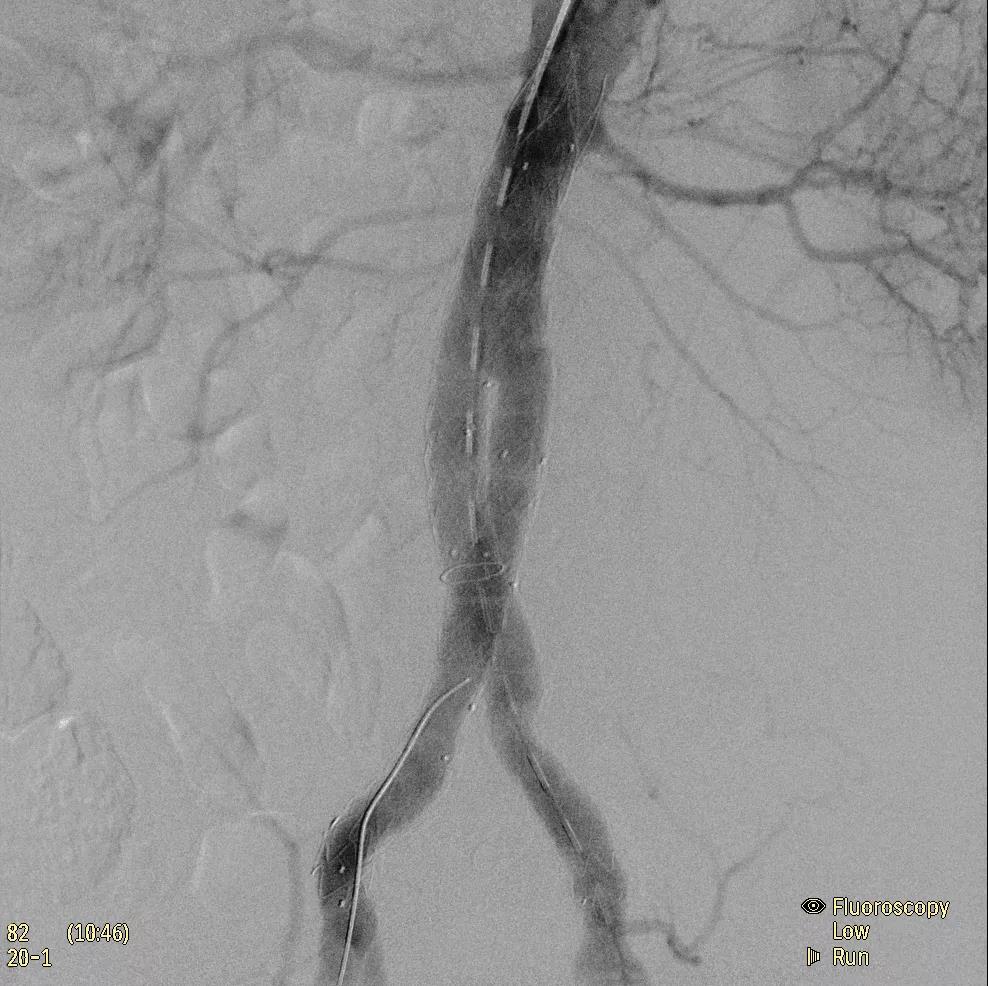

為了獲得清晰的高質量圖像,Zenition 70 采用了與公司Azurion平臺相同的圖像處理算法,可提供患者解剖結構的高清可視化和更大的可視區(qū)域。飛利浦的MetalSmart軟件等功能可確保圖像質量,該軟件可自動調整圖像的對比度和亮度,以便在視野中存在金屬物體(如植入物)時提高圖像質量 - 這一特性使Zenition 70在整形外科中特別有用。